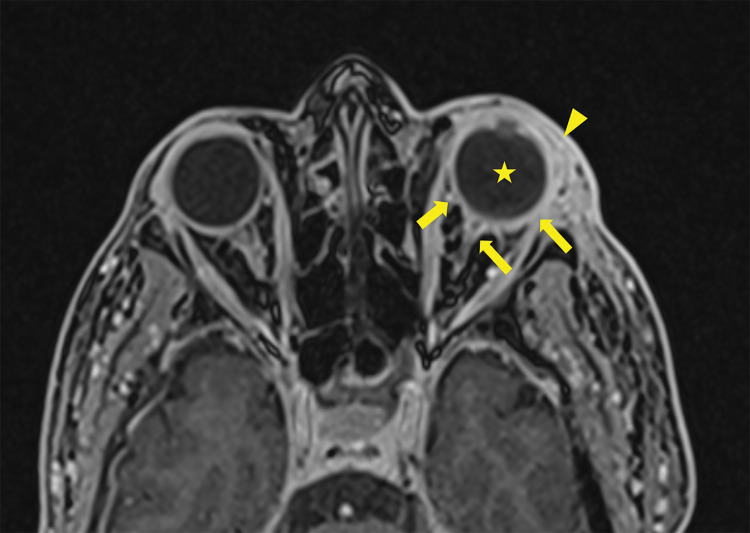

MRI Findings of Endogenous Endophthalmitis as a Complication of Pneumococcal Meningitis.

Teaching point: Endophthalmitis is an uncommon but severe complication of meningitis that can be visualized on MRI.